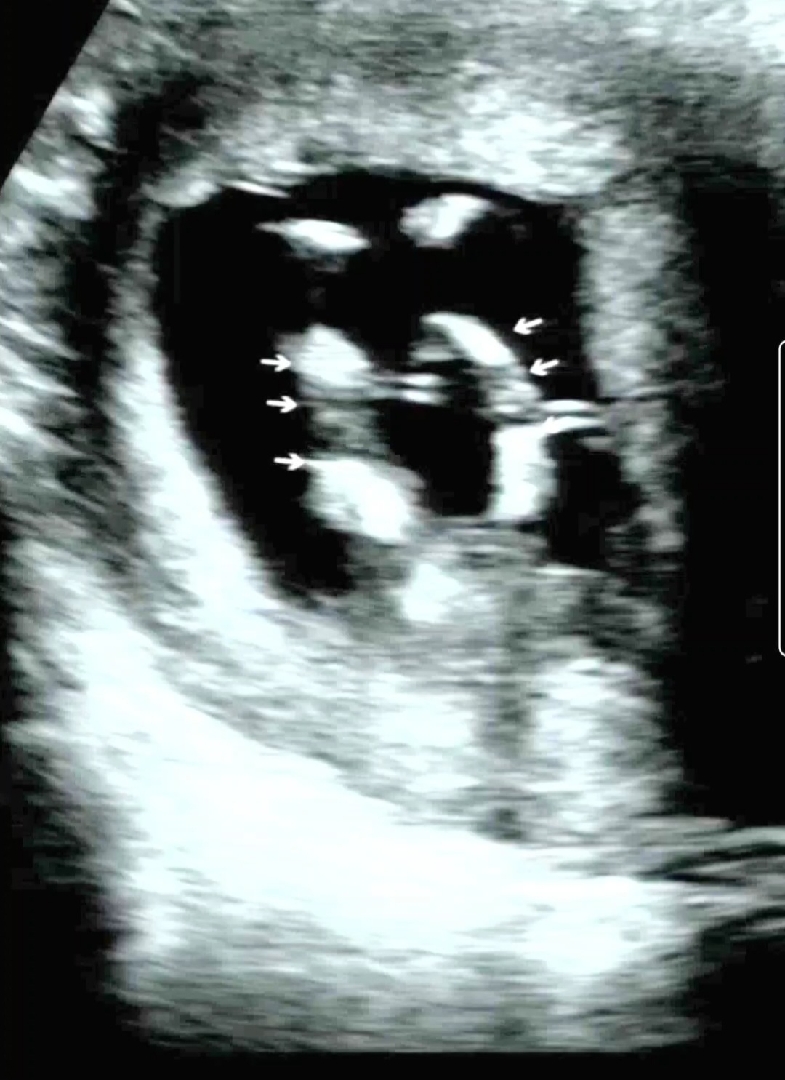

아이 성별 확인 가능한가요?

12주 6일 차인데 기형아 검사 받고 많이 올리시길래 참여해봅니다. 편집하니까...다리 사이 없어 보이기두하고 입체영상보니 그부분이 볼록 튀어 나온 것 같기도 해요... 16주차까진 알 수 없지만 궁금해서 올려봅니다...